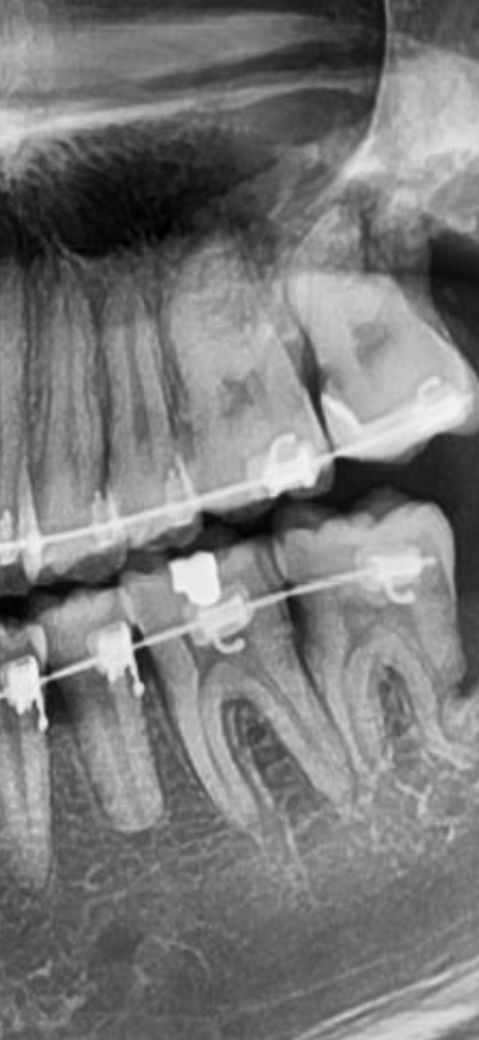

제목그대로 하고있는데 엑스레이상은 왜 검은색처럼 나와요??? 제가 얼마전에 인레이한 병원에서는 아무이상없다거 하시긴하셨는데 불과 일주일전인데 교정한곳에서 찍은사진인데 왜 검게

나오죠? 치실이랑 치간칫솔 진짜 그 인레이한부분은 관리 맨날했는데…. 충치 다시생긴거 아니겠죠?

• 1번 째 사진

검게 나오는 것은 방사선 사진의 특성에의해 소환현상이 나타나서 그런 것 일수도 있습니다.

큰 사진으로는 정확히 판단하기는 어렵지만, 엑스레이 상으로보면 인레이 하방으로 충치가 다시 생긴것처럼 보입니다.

인접면에 있는 검은 부분을 말씀하시는 거라면 꼭 충치라고 볼 수 없습니다. 엑스레이 사진 상에서 나타나는 왜곡(치경부 소환)의 현상일 가능성도 있습니다.

인레이를 한 치아 하방으로 충치가 진행된 것으로 보입니다. 관리를 잘했다고 하더라도 구조상으로 음식물이 잘 빠지지 않는 곳이라면 사진처럼 충치가 생길 수 있습니다. 인레이를 하고 난 다음에 충치가 생겼다면 크라운 치료를 하는 것이 좋을 수 있습니다.

자세한 확인을 위해서 치과에서 진료를 받아보는 것을 권유드립니다.